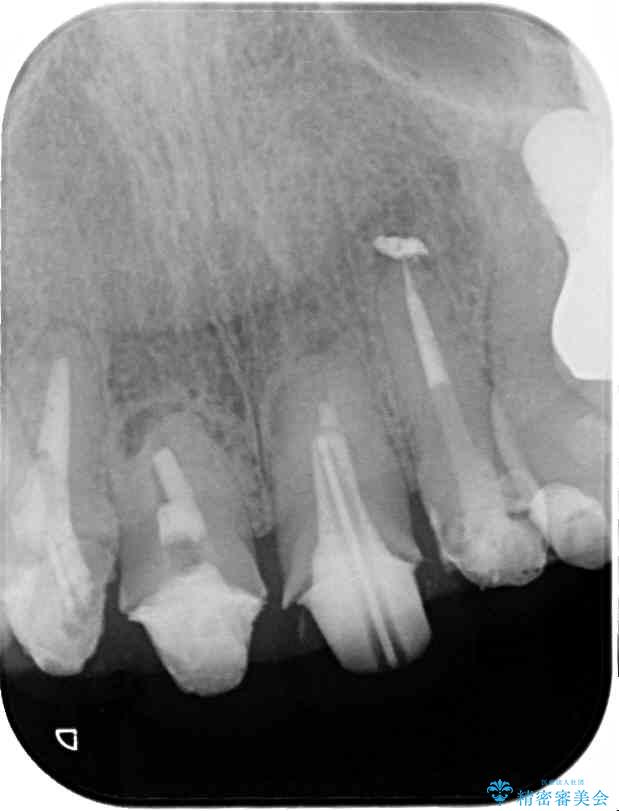

治療前

• 仮歯のまま放置した前歯 オールセラミッククラウンで自然な前歯に 治療前画像

治療計画

仮歯が不適合で歯肉が腫脹していたため、しっかりと調整した新しい仮歯にして腫れを改善した上で、オールセラミッククラウンにて補綴することとしました。